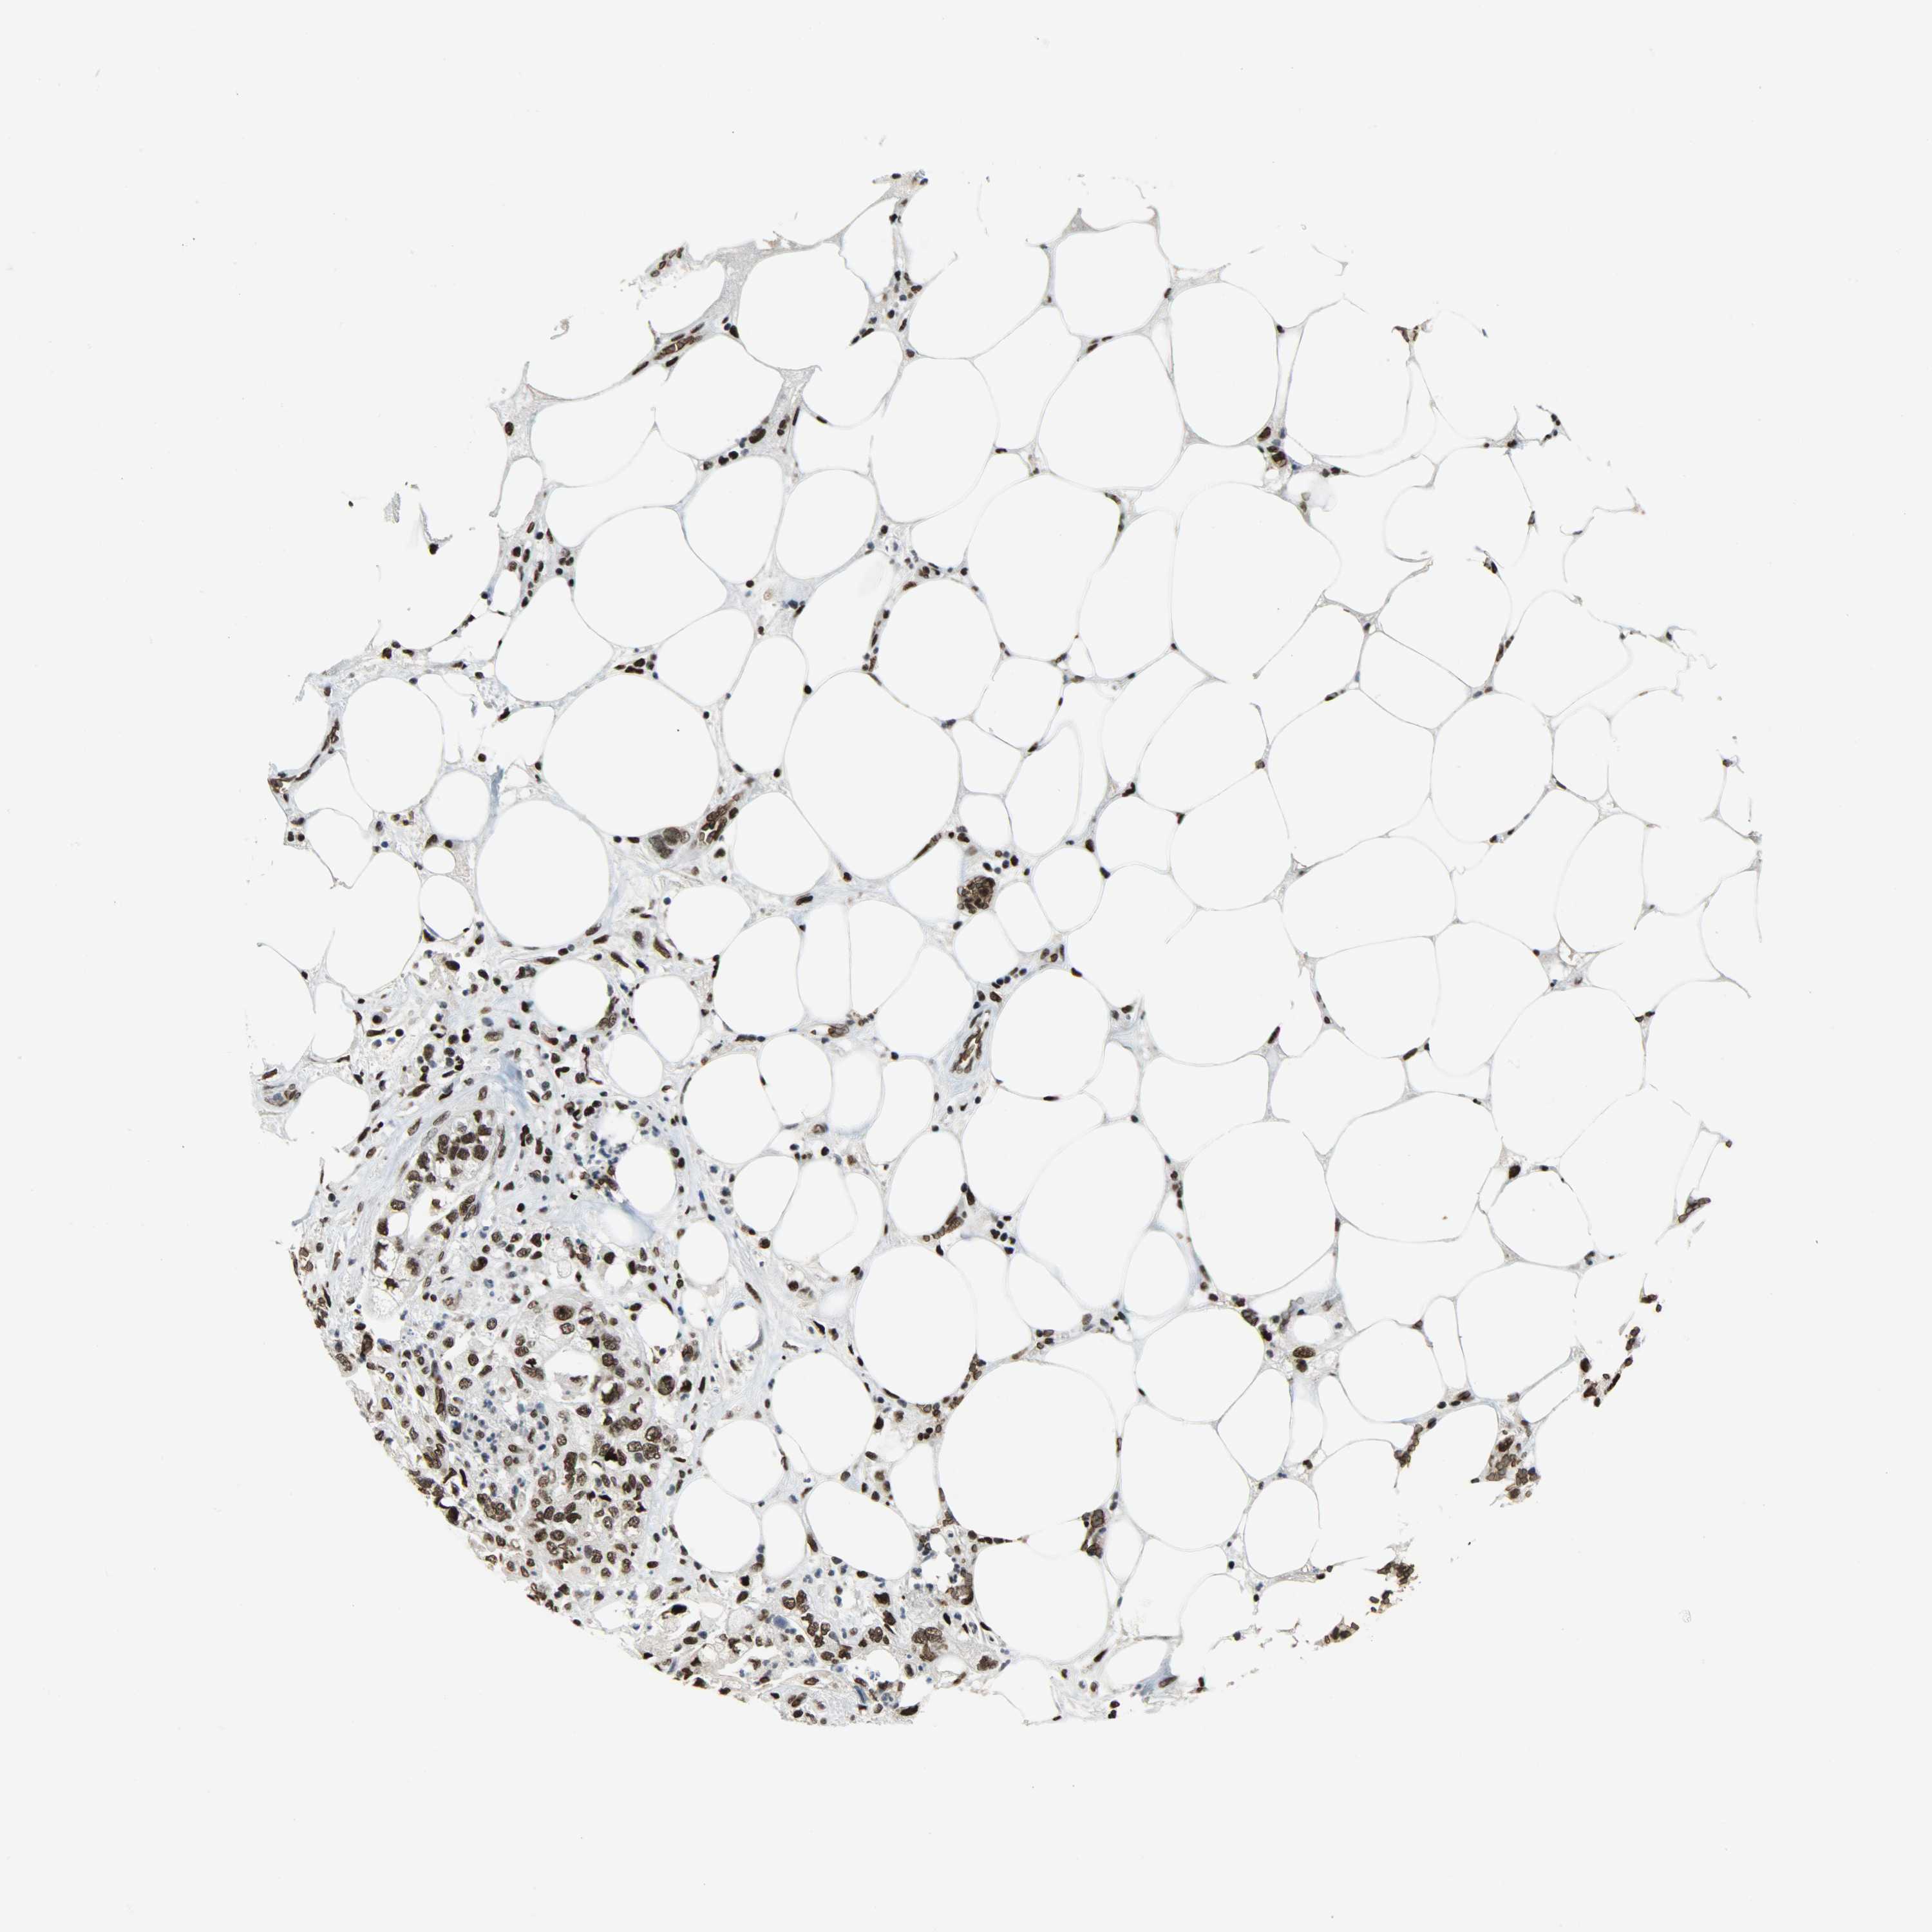

PANCREATIC CANCER - Protein expressioni

A mouse-over function shows sample information and annotation data. Click on an image to view it in a full screen mode. Samples can be filtered based on level of antibody staining by selecting one or several of the following categories: high, medium, low and not detected. The assay and annotation is described here.

Note that samples used for immunohistochemistry by the Human Protein Atlas do not correspond to samples in the TCGA dataset.

Antibody stainingi

Antibody staining in the annotated cell types in the current human tissue is reported as not detected, low, medium, or high, based on conventional immunohistochemistry profiling in selected tissues. This score is based on the combination of the staining intensity and fraction of stained cells.

Each image is clickable and will lead to virtual microscopy that enables deeper exploration of all samples and also displays staining intensity scores, fraction scores and subcellular localization as well as patient and tissue information for each sample.

Antibody HPA069985

Antibody CAB005883

Antibody CAB078687

Antibody CAB080398

Staining

High

Medium

Low

Not detected

Intensity

Strong

Moderate

Weak

Negative

Quantity

>75%

75%-25%

<25%

None

Location

Nuclear

Cytoplasmic/membranous

Cytoplasmic/membranous,nuclear

Adenocarcinoma, NOS

Adenocarcinoma, metastatic, NOS